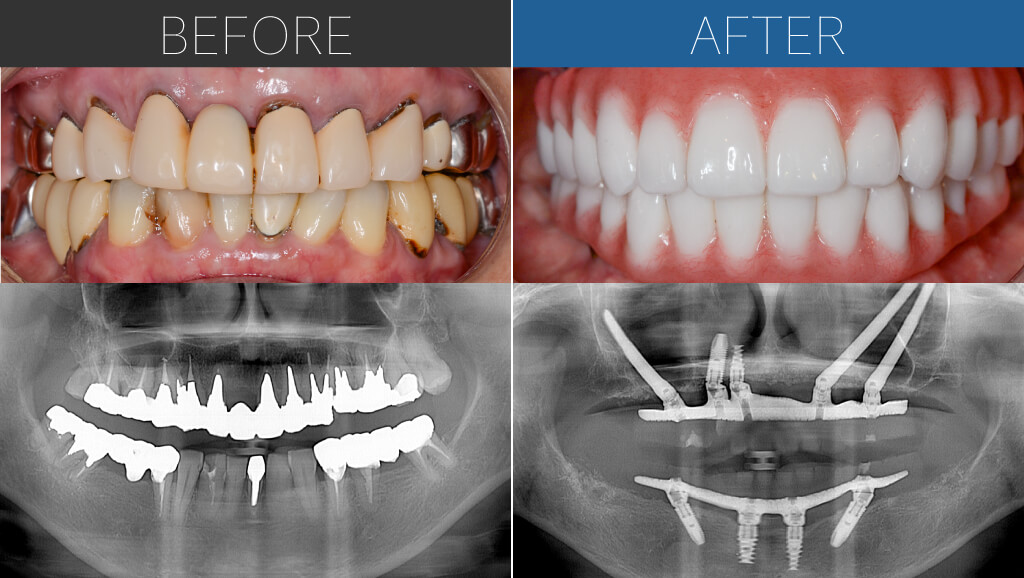

– Upper:All-on-4 + Zygoma

– Lower:All-on-4

Age:40s

| 治療内容 | 重度歯周病のため、上顎は右側は通常の埋入が難しくザイゴマインプラント。下顎は基本的な4本埋入によるオールオン4。上下ともに即時荷重により手術当日に仮歯を固定。 |